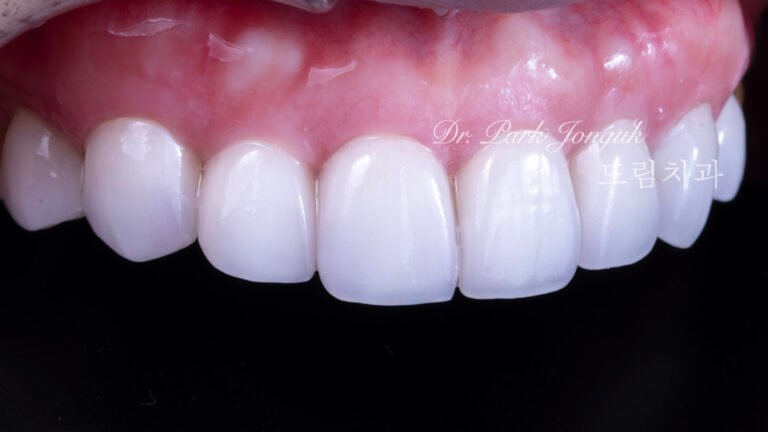

라미네이트 재시술 레이저 제거

치아 손상 없이 라미네이트 재시술을 가능하게 하는 핵심 기술 라미네이트 재시술에서 가장 중요한 단계는새로운 라미네이트를 “어떻게 만드느냐”가 아니라,기존 라미네이트를 어떻게...